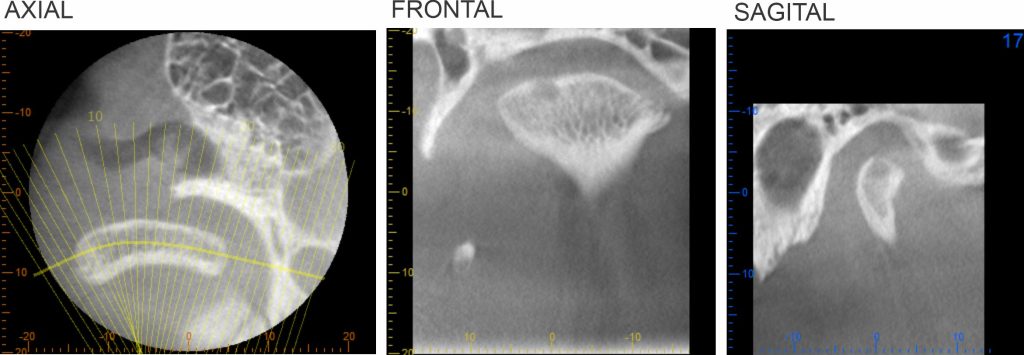

El Centro Radiológico Diagnóstico Oral 3D, es una empresa antioqueña que ofrece a sus pacientes desde el año 2009, tecnología de vanguardia en radiografías tridimensionales con calidad fotográfica. Las posibilidades para mejorar la eficacia en los diagnósticos bucales son evidentes, también lo son las posibilidades de manipulación de imagen. El sistema de imágenes en 3D ofrece detalles sin precedentes, convirtiéndola en la opción idónea para la mayoría de aplicaciones odontológicas, incluyendo implantes, tratamiento de conductos, ortodoncia, odontopediatría, periodoncia y cirugía

El mayor beneficiado con el uso de esta tecnología es el paciente, el cual podrá ser evaluado en todas sus dimensiones con una baja dosis de radiación, con un costo accesible y sin contaminar  el medio ambiente. Dependiendo de la necesidad del paciente, hay varios tipos de tomografías y los especialistas en el área odontológica hacen uso de ellas según su especialidad.

La radiología oral especializada es fundamental para una práctica dental integral, proporcionando información específica que influye en la toma de decisiones clínicas y mejora los resultados del tratamiento para los pacientes